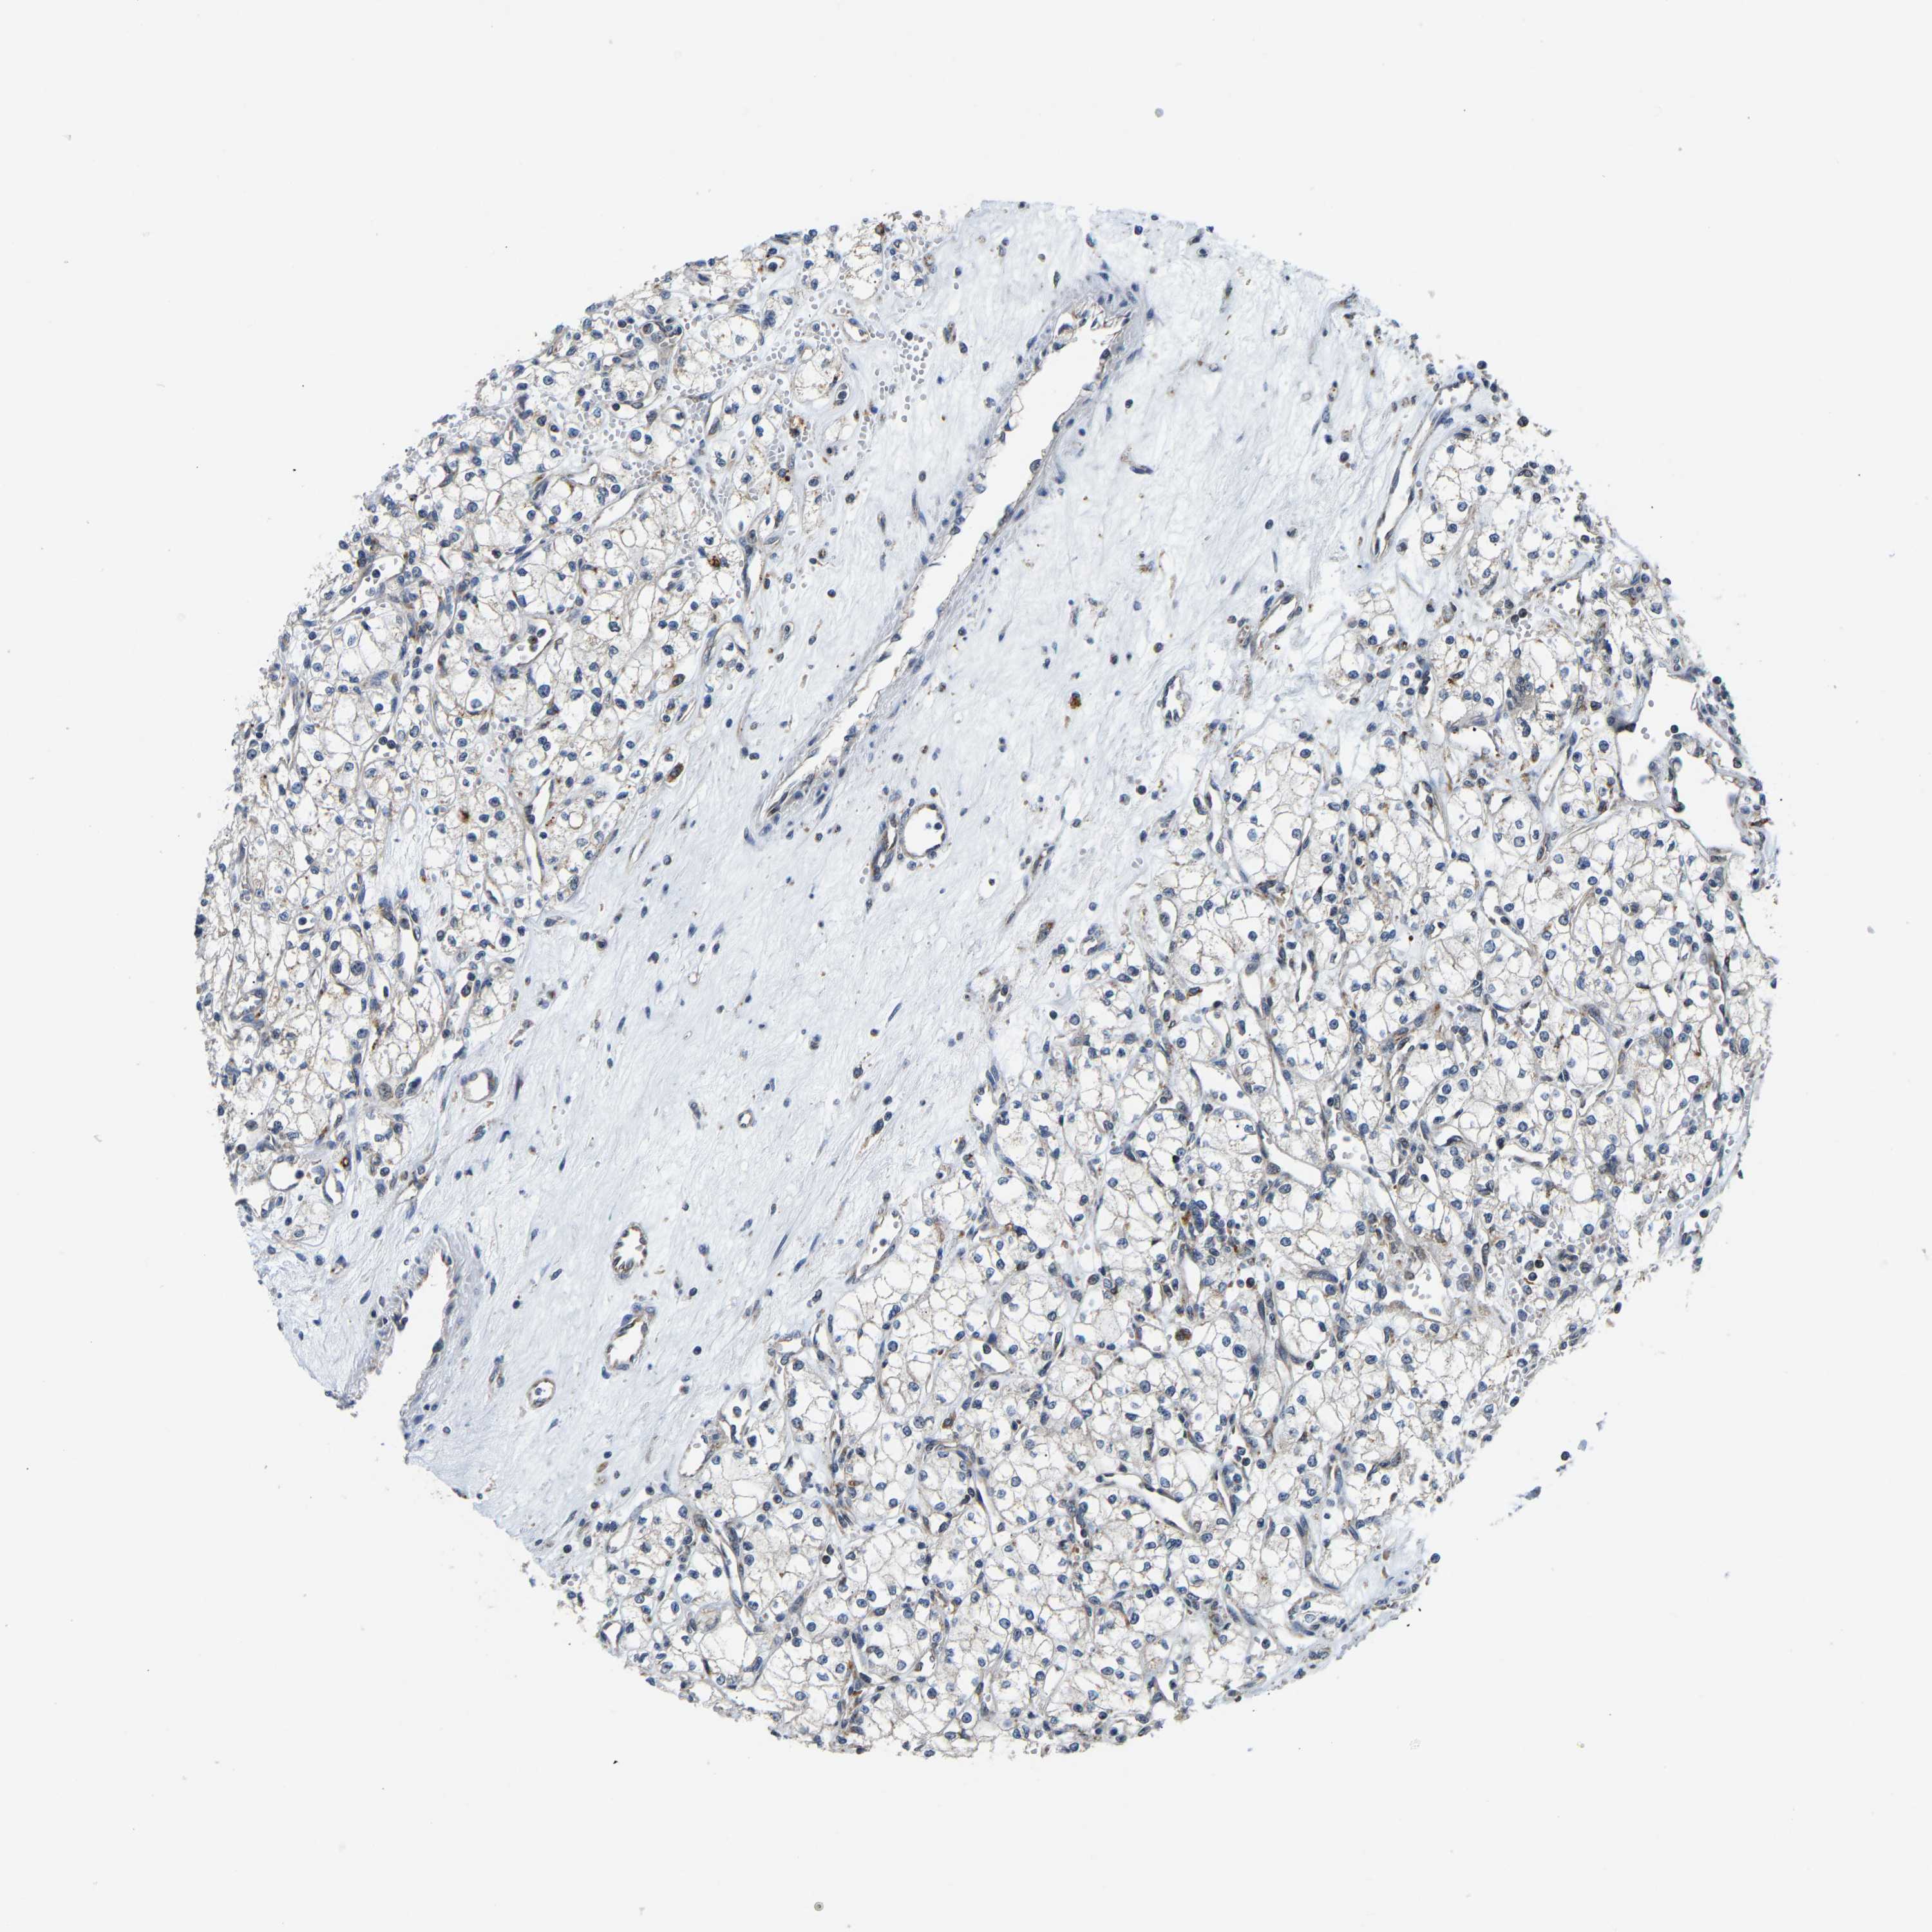

KIDNEY RENAL CLEAR CELL CARCINOMA (TCGA) - Interactive survival scatter ploti

The Survival Scatter plot shows the clinical status (i.e. dead or alive) for all individuals in the patient cohort, based on the same data that underlies the corresponding Kaplan-Meier plots. Patients that are alive at last time for follow-up are shown in blue and patients who have died during the study are shown in red.

The x-axis shows the expression levels (FPKM) of the investigated gene in the tumor tissue at the time of diagnosis. The y-axis shows the follow-up time after diagnosis (years). Both axes are complimented with kernel density curves demonstrating the data density over the axes. The top density plot shows the expression levels (FPKM) distribution among dead (red) and alive patients (blue). The right density plot shows the data density of the survived years of dead patients with high and low expression levels respectively, stratified using the cutoff indicated by the vertical dashed line through the Survival Scatter plot. This cutoff is automatically defined based on the FPKM cutoff that minimizes the p-score. The cutoff can be changed by dragging the vertical line or by entering a cutoff value in the square labeled "Current cut-off".

Under the Survival Scatter plot the p-score landscape (black curve; left axis) is shown together with dead median separation (red curve; right axis). Dead median separation is the difference in median mRNA expression between patients who have died with high and low expression, respectively. It is calculated as follows: median FPKM expression of dead patients with high expression - median FPKM expression of dead patients with low expression. This is intended to aid the user in visually exploring custom cutoffs and the associated p-scores and dead median separation.

Individual patient data is displayed and can be filtered by clicking on one or more of the category buttons on the top of the page. Categories describing expression level and patient information include: high, low, alive, dead, female, male and tumor stages. The scale of the x-axis can be toggled between linear and log-scale by clicking on the "x log" button. Mouse-over function shows TCGA ID, patient information and mRNA expression (FPKM) for each patient.

& Survival analysisi

Kaplan-Meier plots summarize results from analysis of correlation between mRNA expression level and patient survival. Patients were divided based on level of expression into one of the two groups "low" (under cut off) or "high" (over cut off). X-axis shows time for survival (years) and y-axis shows the probability of survival, where 1.0 corresponds to 100 percent.

GIMAP7 is potential prognostic, high expression is favorable in Kidney Renal Clear Cell Carcinoma (TCGA)

Best expression cut offi

Based on the FPKM value of each gene, patients were classified into two groups and association between prognosis (survival) and gene expression (FPKM) was examined. The best expression cut-off refers the FPKM value that yields maximal difference with regard to survival between the two groups at the lowest log-rank P-value. Best expression cut-off was selected based on survival analysis .

When clicking on this number, the vertical dashed line indicating cut-off, the interactive survival plot, and the Kaplan-Meier curve will be adjusted to show results based on the best expression cut-off.

: 29.46

Median expressioni

Median expression refers to the median FPKM value calculated based on the gene expression (FPKM) data from all patients in this dataset. When clicking on this number, the vertical dashed line indicating cut-off, the interactive survival plot, and the Kaplan-Meier curve will be adjusted to show results based on the median expression.

: N/A

Median follow up timei

Median follow up time refers to the median time (years) after diagnosis with this type of cancer, based on clinical data from all patients in this dataset.

P scorei

Log-rank P value for Kaplan-Meier plot showing results from analysis of correlation between mRNA expression level and patient survival.

N/A

5-year survival highi

5-year survival for patients with higher expression than the expression cutoff.

For melanoma and glioma, 3-year survival is shown.

5-year survival lowi

5-year survival for patients with lower expression than the expression cutoff.

TCGA RNA samplesi

RNA-seq data is reported as average FPKM (number Fragments Per Kilobase of exon per Million reads), generated by the The Cancer Genome Atlas (TCGA) .

Normal distribution across the dataset is visualized with box plots, shown as median and 25th and 75th percentiles. Points are displayed as outliers if they are above or below 1.5 times the interquartile range. FPKM values of the individual samples are presented next to the box plot.

Average pTPM 54.2

Number of samples 521